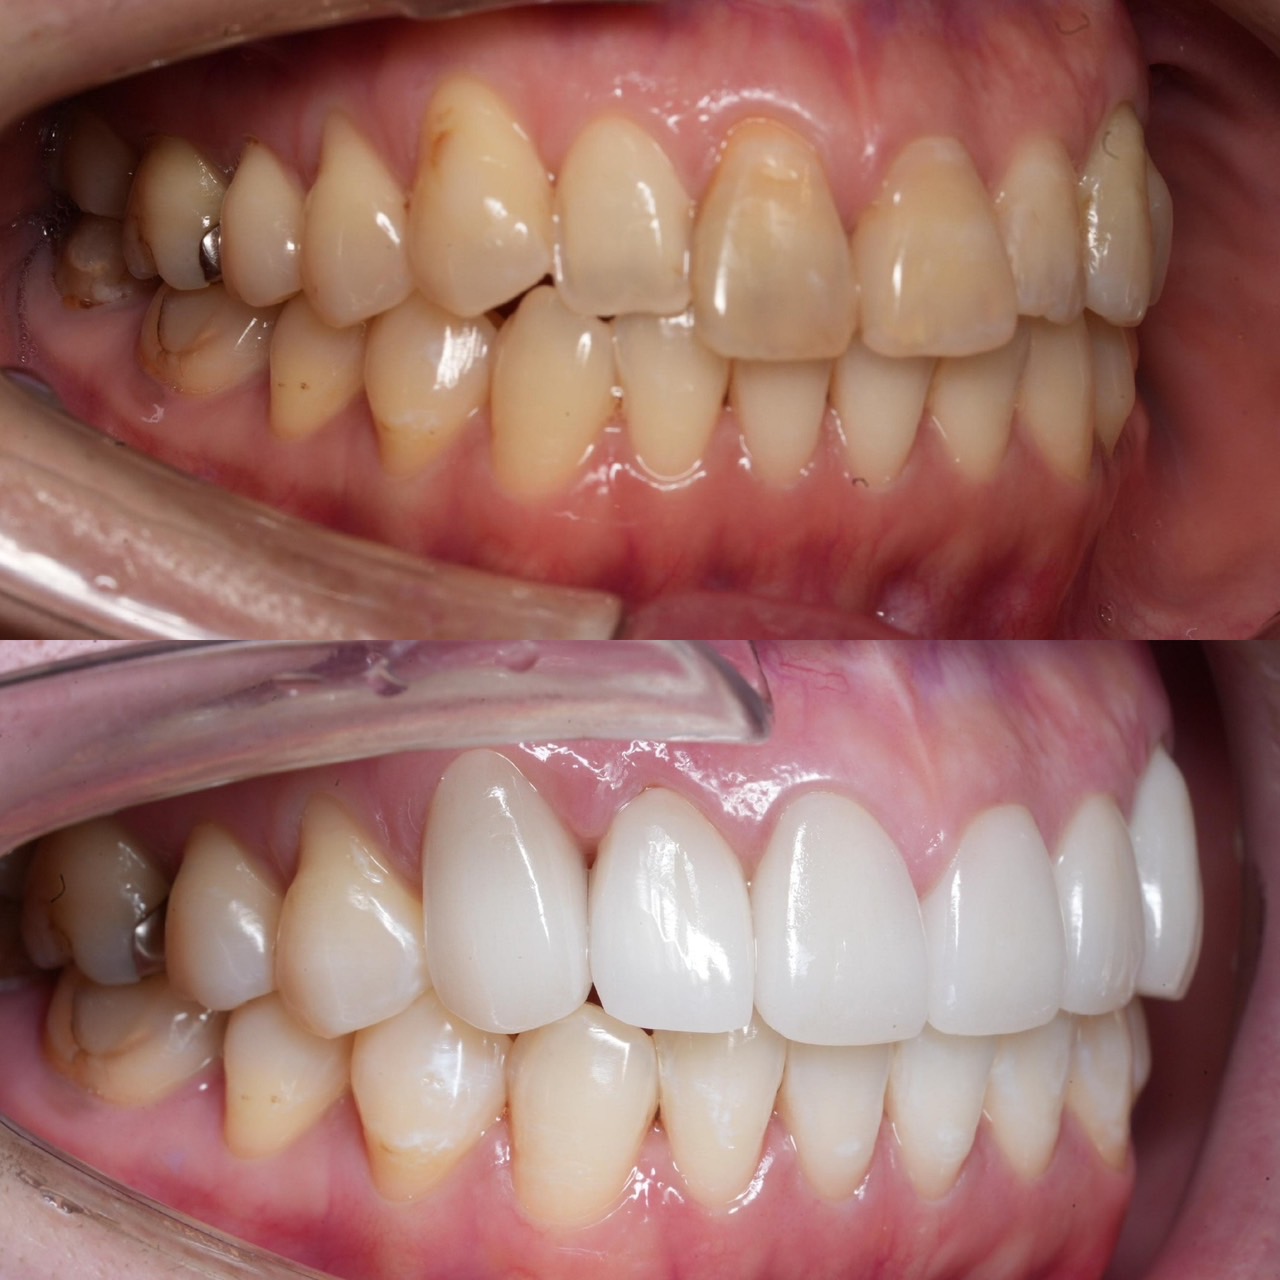

Case022 – インプラント

広島からの患者様です。

前歯を綺麗にしたい。インプラントをしたい。

という主訴で東京の歯医者をいろいろ調べて当院を選んでくださいました。

毎回、遠い中しっかり通ってくださり、選んで頂けた嬉しさと、その気持ちに応えたいという想いで診療させて頂きました。

前歯はご希望のお色でラミネートベニアでは出せない透明感のあるセラミックに上下左側7はインプラントをさせて頂きました。

左上は破折で温存不可。

骨も少なかったので、サイナスリフトも行い計五回の来院で被せ物を入れさせて頂きました。

左下は前回のクリニックでの埋入位置が深すぎて食べカスも毎回詰まる、セルフメンテナンスではら汚れも取れない。インプラント周囲炎にもなっていたので、一度前のインプラントを除去し、そこから新しくインプラントを埋入し、診療させて頂きました。